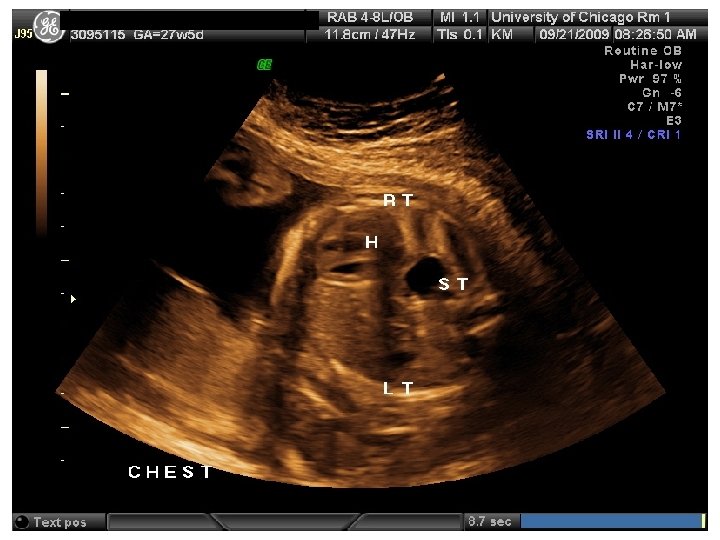

QUIZ What is Your Diagnosis? Case: Patient J. F. 30 years old, at 32 week gestation. Presented with the following pictures.

Answer: a) Trisomy 21 b) Non-immune Hydops c) Paravo virus Infection